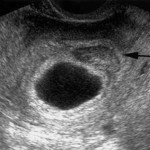

Фотографии: